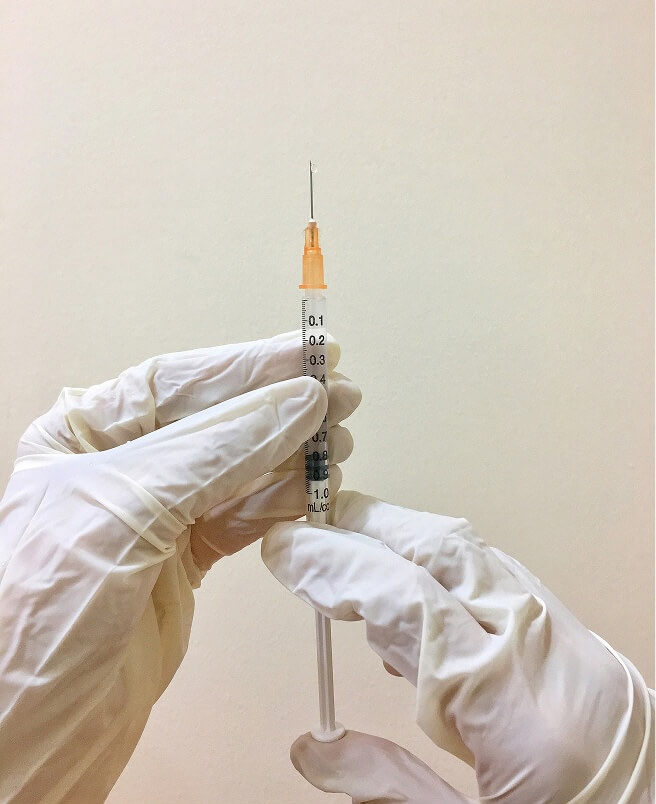

After a consultation and review of lab results and goals, your Aerwell provider selects evidence‑based peptides such as muscle‑building, metabolic, recovery, or immune‑support peptides, and outlines dosing, administration, and monitoring. Many peptide protocols are delivered as subcutaneous injections over several weeks to months, alongside lifestyle guidance and periodic lab checks.

Usually via subcutaneous injections, with cycles guided by your provider and monitored for response.